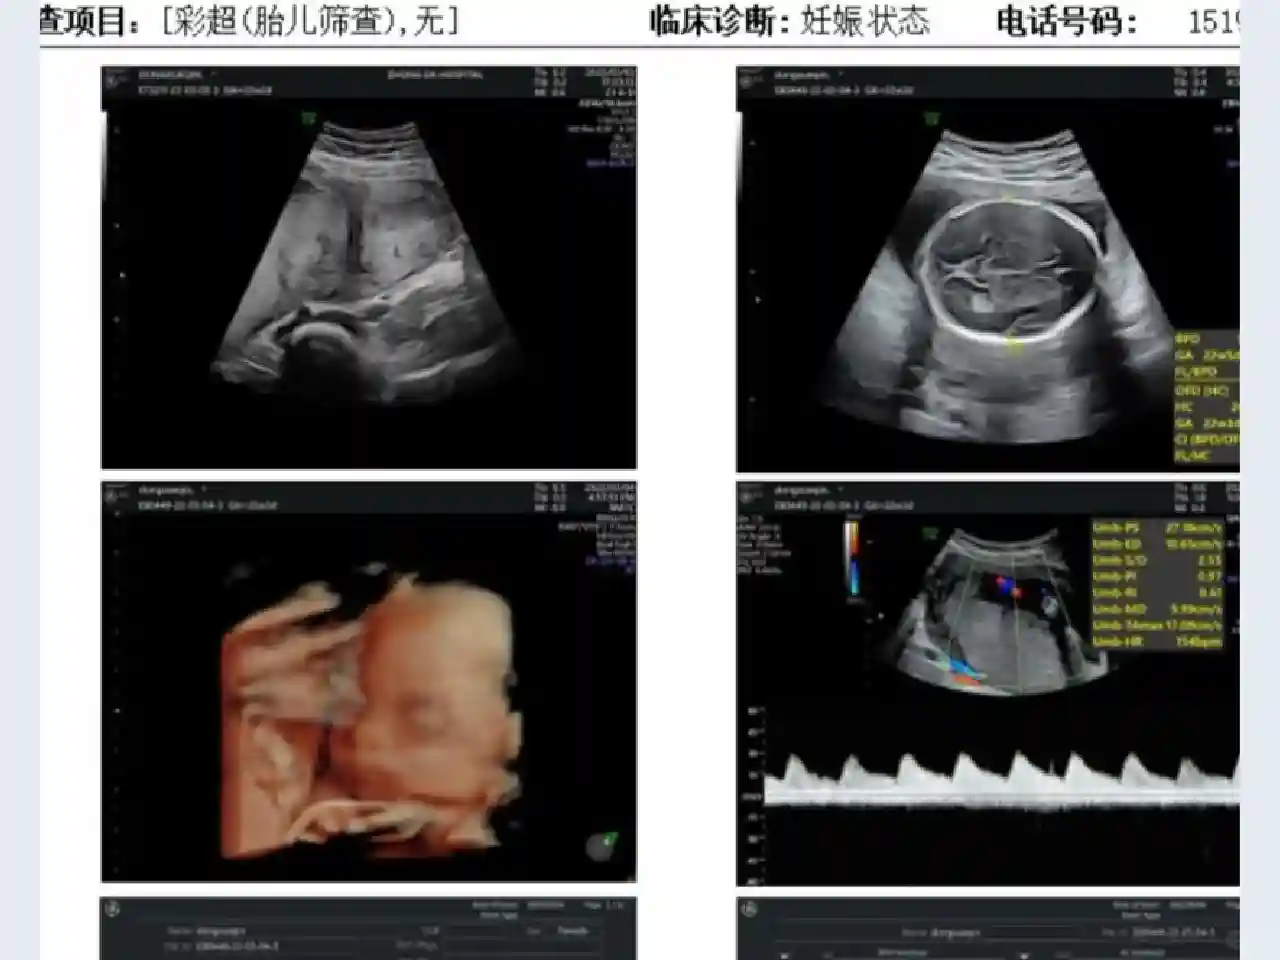

去检查的时候做B超的时候医生就告诉我我子宫有点问题,是完全纵隔子宫(没怀孕之前做过B超但是都没查出来有什么问题)。后面就挂了专家号看,医生说怀上了就没什么问题,后面也就正常上班正常产检。

前面的产检一切都很顺利,只有大排畸做了两天才看完,宝宝一直趴着不给看。结果几天后,也就是23周的时候发生了意外,晚上回去就感觉宝宝今天好像没怎么动,怎么戳他都没反应,用胎心仪也找不到胎心,瞬间就慌了,连夜打车去了医院,可能是凌晨去的打扰到她休息了,结果去的时候还被抱怨说我现在这个月份数什么胎动呀,还不规律,然后让我躺床上听胎心,结果医生也找不到,医生也瞬间清醒了,让我去抽血做B超。做B超的时候发现胎停了,那个医生看我一个人不放心还让助理陪我去了诊室,后面医生就让住院引产,我说我等我先生回来再住院,就自己一个人出去了,出了医院还摔了一跤情绪瞬间就崩溃了。路上就给先生打了电话,回了宿舍等着他回来,中途医院不放心打电话给我让我一定要去医院。宝宝引产出来医生说是脐带扭转太多,窒息死亡的。后面我们也进行了胎儿染色体筛查,没有查出太大的问题,可能就是医生说的偶然事件吧。我的小老虎就这样离开了,医生只告诉我是个男宝宝,我都没来得及看一眼,先生说他在走廊外面远远看到医生手里捧着宝宝,都已经长头发了呢。